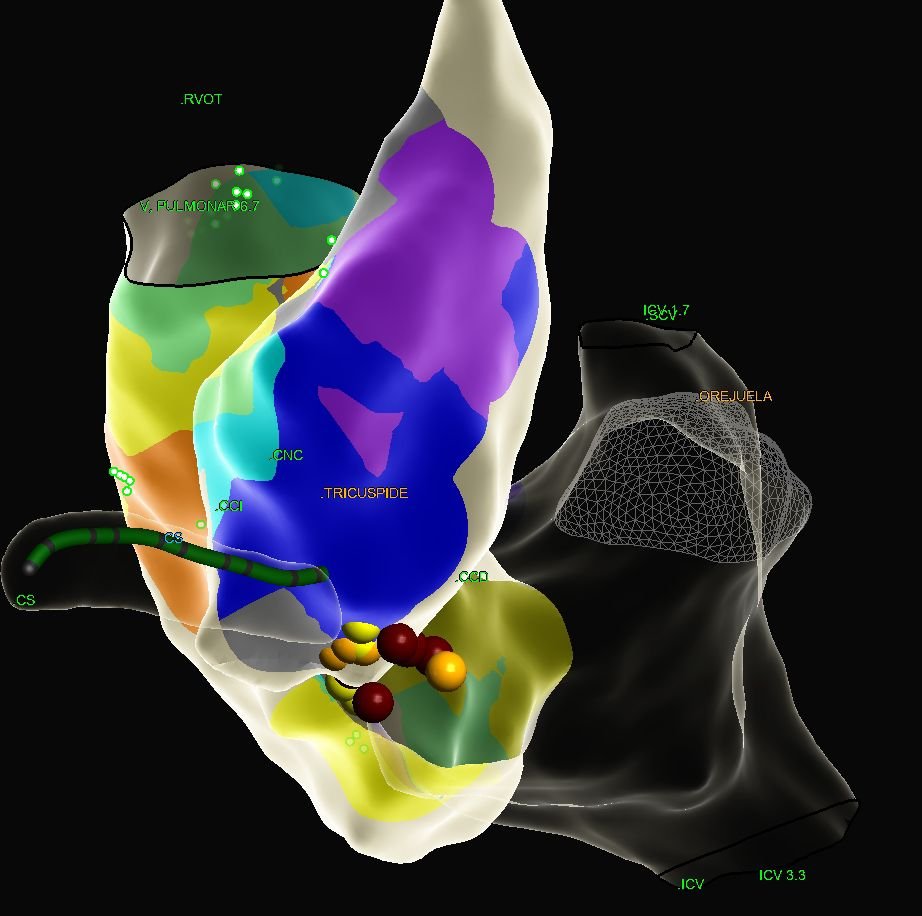

De acuerdo con Carrasco Chávez, actualmente el tratamiento más efectivo es el estudio electrofisiológico con ablación, procedimiento que se realiza en el Hospital CYNTAR con el apoyo de un mapeo del sistema eléctrico del corazón para identificar el origen de la arritmia y cauterizar la zona responsable, evitando así su recurrencia.

Esta tecnología solo existe en cuatro centros de todo México, siendo CYNTAR el único en el noroeste del país, donde el abordaje de estas enfermedades ha evolucionado, pasando de priorizar medicamentos a considerar la ablación como tratamiento principal, utilizando los fármacos únicamente como apoyo temporal.